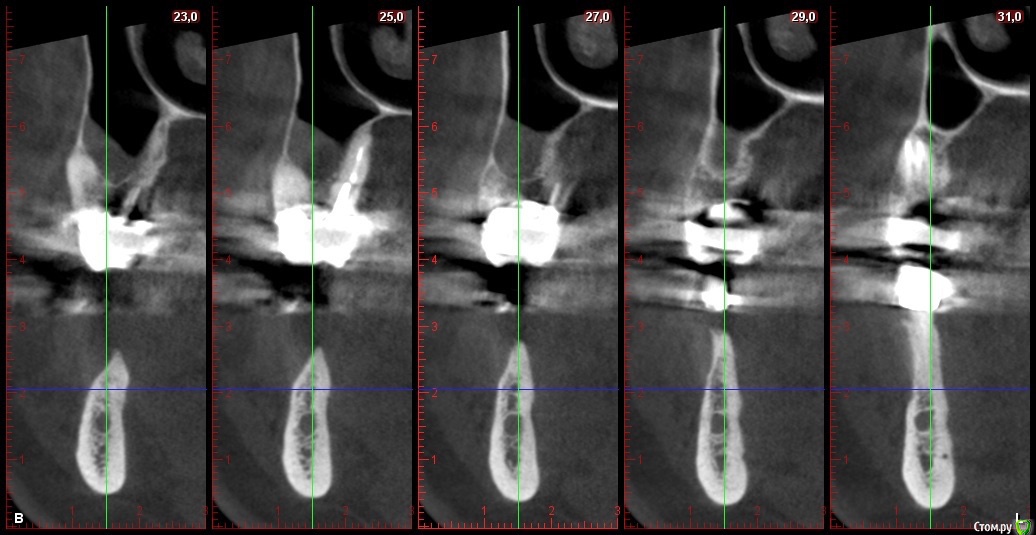

Глеб Митрофанов Опубликовано 22 октября, 2015 Автор Поделиться Опубликовано 22 октября, 2015 Срезы кт Ссылка на комментарий

basha.ru Опубликовано 23 октября, 2015 Поделиться Опубликовано 23 октября, 2015 Спасибо за кейс.Скажите пожалуйста какая высота кости до нижнечелюстного канала?Спасибо. Ссылка на комментарий

Глеб Митрофанов Опубликовано 23 октября, 2015 Автор Поделиться Опубликовано 23 октября, 2015 (изменено) Спасибо за кейс.Скажите пожалуйста какая высота кости до нижнечелюстного канала?Спасибо.До канала , в самой низшей точке - 4,5-5 мм Изменено 23 октября, 2015 пользователем Глеб Митрофанов Ссылка на комментарий